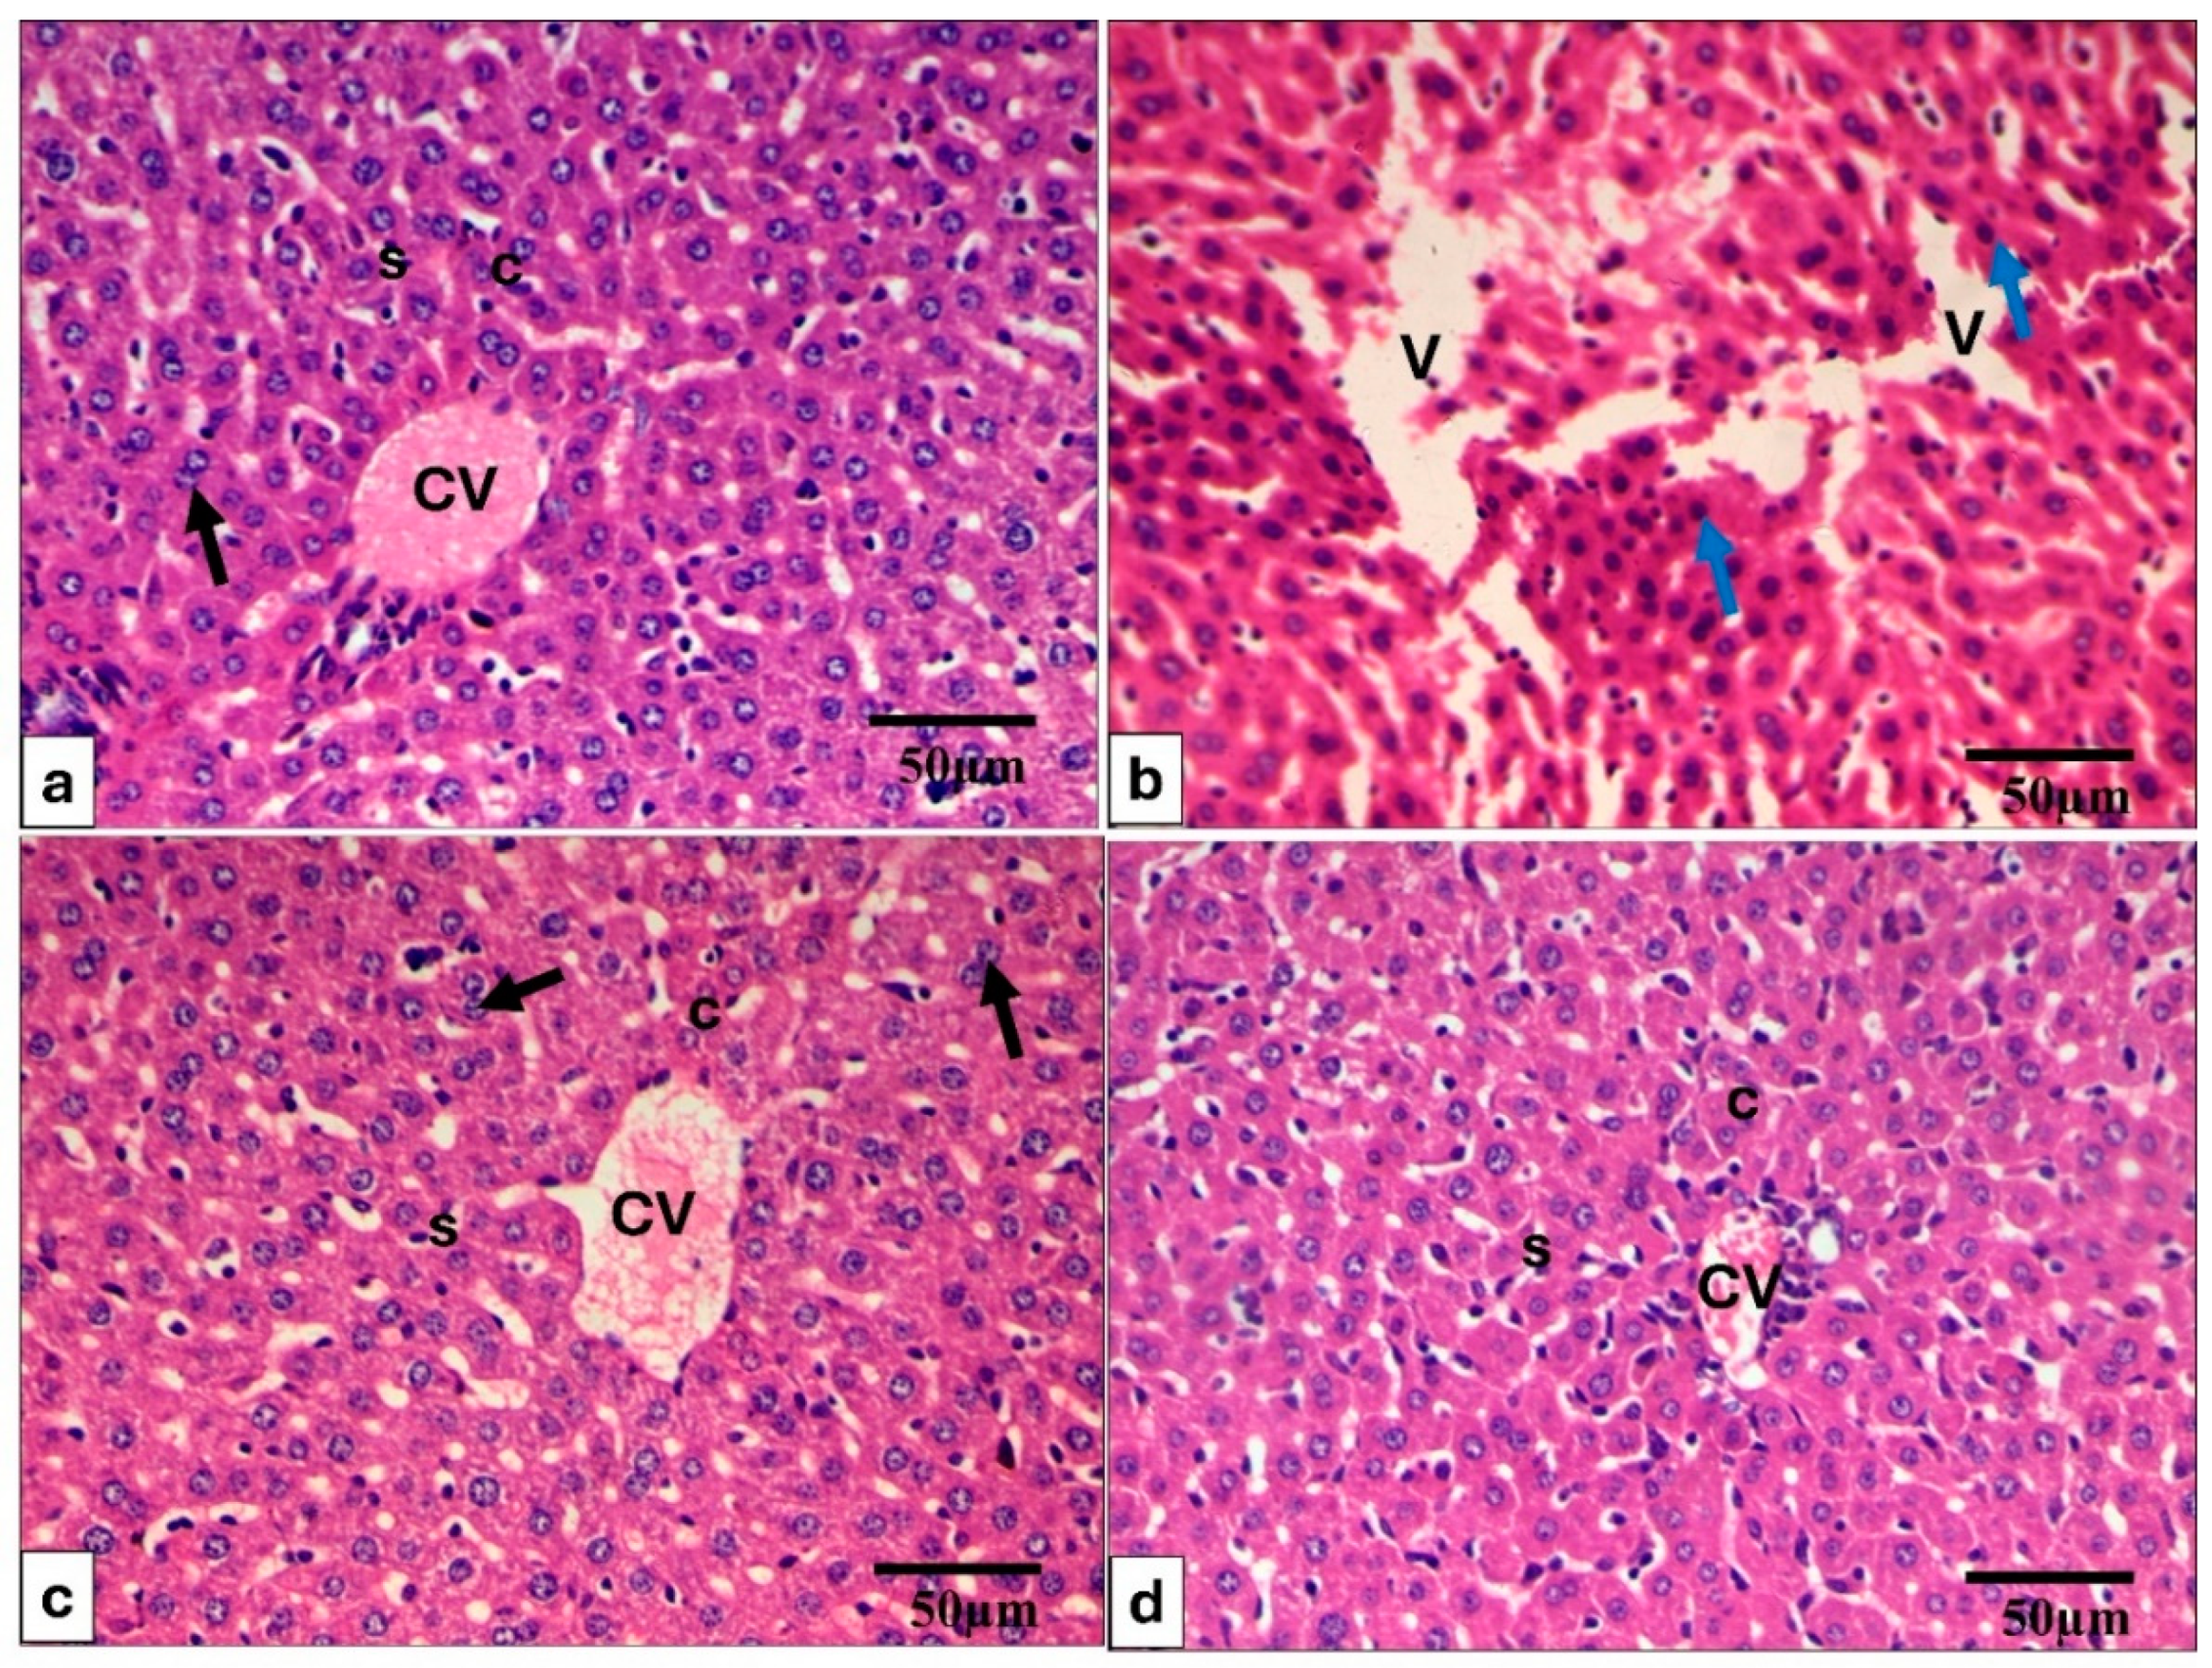

2.2.2. Histopathology